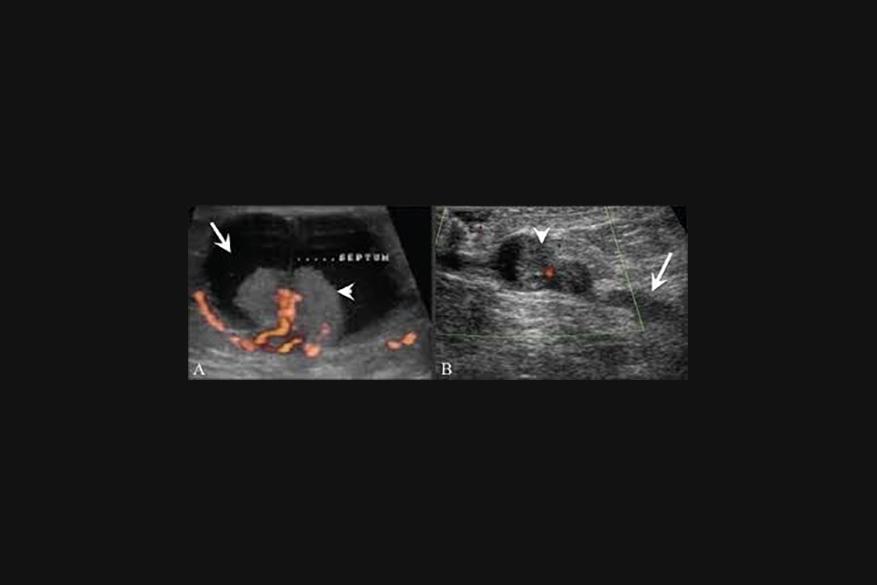

Ένα ενδοπορικό θήλωμα( Intraductal Papilloma ) είναι ένας μικρός, καλοήθης όγκος που σχηματίζεται σε έναν γαλακτοφόρο πόρο στο στήθος. Αυτοί οι όγκοι αποτελούνται απο αδένα, ινώδη ιστό και αιμοφόρα αγγεία. Εμφανίζονται συχνότερα σε γυναίκες ηλικίας 35 έως 55 ετών. Δεν υπάρχουν γνωστοί παράγοντες κινδύνου για τα ενδοπορικά θηλώματα.